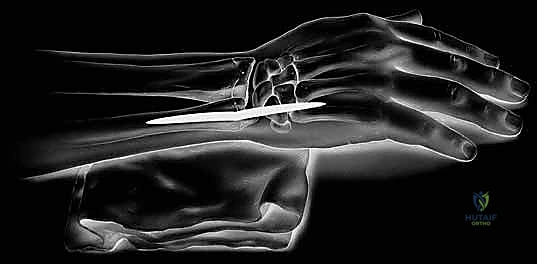

يُعد مفصل الرسغ والساعد من أكثر البنيات التشريحية تعقيدًا ودقة في جسم الإنسان. إنه يلعب دورًا محوريًا في كل حركة تقوم بها يدك، بدءًا من الحركات الدقيقة مثل الكتابة أو الإمساك بإبرة، وصولاً إلى الحركات القوية مثل رفع الأثقال أو استخدام الأدوات الثقيلة. عندما يتعرض هذا النظام الميكانيكي الحيوي الدقيق للألم أو عدم الاستقرار، فإن جودة حياة المريض تتأثر بشكل جذري.

في قلب هذه المشكلات الميكانيكية غالبًا ما يكمن مفصل الزند والكعبرة البعيد (Distal Radioulnar Joint - DRUJ). هذا المفصل المحوري هو المسؤول الأول عن حركات دوران الساعد.

تُعد جراحة استبدال رأس الزند الصناعي (Ulnar Head Replacement) حلاً ثوريًا ومتقدمًا للمرضى الذين يعانون من آلام مزمنة وعدم استقرار شديد في هذا المفصل، خاصة أولئك الذين استنفدوا خيارات العلاج التحفظي أو عانوا من فشل عمليات جراحية سابقة (مثل عمليات الاستئصال القديمة). هذه الجراحة لا تقتصر على مجرد إزالة العظم التالف؛ بل هي عملية "إعادة بناء" شاملة تهدف إلى استعادة التوازن الميكانيكي، وتخفيف الألم، وإعادة القدرة على الحركة الطبيعية للساعد.

لفهم أهمية جراحة استبدال رأس الزند، يجب أولاً التعمق في تشريح الساعد والرسغ. يتكون الساعد من عظمين طويلين: الكعبرة (Radius) والزند (Ulna).

مفصل الزند والكعبرة البعيد (DRUJ) هو المفصل الذي يربط بين هذين العظمين بالقرب من الرسغ. وظيفته الأساسية هي السماح للكعبرة بالدوران حول الزند الثابت نسبيًا. هذا الدوران هو ما يسمح لك بقلب راحة يدك لأعلى (الاستلقاء - Supination) أو لأسفل (الكب - Pronation).

لا يمكن الحديث عن مفصل الزند دون ذكر مجمع الغضروف الليفي الثلاثي (Triangular Fibrocartilage Complex - TFCC). هذا المجمع عبارة عن شبكة معقدة من الأربطة والغضاريف التي تعمل كـ "وسادة" و "مثبت" رئيسي لمفصل الزند والكعبرة البعيد.

عندما يتم تدمير رأس الزند بسبب التهاب المفاصل، أو عندما يتم استئصاله في جراحات سابقة، يفقد الـ TFCC نقطة ارتكازه، مما يؤدي إلى عدم استقرار كارثي في الساعد. هنا تبرز عبقرية الأستاذ الدكتور محمد هطيف في الجراحة، حيث لا يقوم فقط بتركيب المفصل الصناعي، بل يعمل على إعادة بناء وتثبيت الأنسجة الرخوة والأربطة المحيطة لضمان استقرار المفصل الجديد.